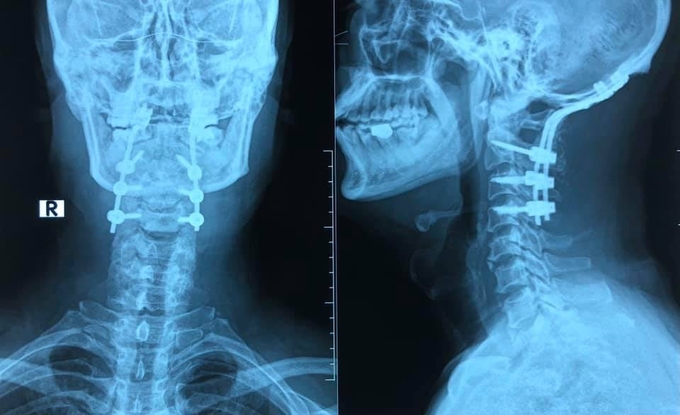

Các bác sĩ khoa Ngoại thần kinh đã tiến hành phẫu thuật cố định chẩm - cổ. Cột sống cổ C2 C3 C4 được cố định bằng vít qua cuống cùng với vít xương chẩm, ghép xương phía sau. Đây là kỹ thuật bắt vít có tác dụng cố định vững chắc nhất về lực.

Phim X-quang chụp sau khi bệnh nhân được cố định, làm vững cột sống. Ảnh: Bác sĩ cung cấp.